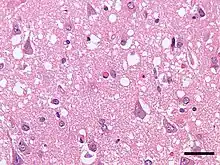

Micrograph showing spongiform degeneration (vacuoles that appear as holes in tissue sections) in the cerebral cortex of a patient who had died of Creutzfeldt–Jakob disease. H&E stain, scale bar = 30 microns (0.03 mm).

Transmissible spongiform encephalopathies (TSEs), also known as prion diseases,[1] are a group of progressive, incurable, and fatal conditions that are associated with the prion hypothesis and affect the brain and nervous system of many animals, including humans, cattle, and sheep. According to the most widespread hypothesis, they are transmitted by prions, though some other data suggest an involvement of a Spiroplasma infection.[2] Mental and physical abilities deteriorate and many tiny holes appear in the cortex causing it to appear like a sponge when brain tissue obtained at autopsy is examined under a microscope. The disorders cause impairment of brain function which may result in memory loss, personality changes, and abnormal or impaired movement which worsen over time.[3]

The degenerative tissue damage caused by human prion diseases (CJD, GSS, and kuru) is characterised by four features: spongiform change (the presence of many small holes), the death of neurons, astrocytosis (abnormal increase in the number of astrocytes due to the destruction of nearby neurons), and amyloid plaque formation. These features are shared with prion diseases in animals, and the recognition of these similarities prompted the first attempts to transmit a human prion disease (kuru) to a primate in 1966, followed by CJD in 1968 and GSS in 1981. These neuropathological features have formed the basis of the histological diagnosis of human prion diseases for many years, although it was recognized that these changes are enormously variable both from case to case and within the central nervous system in individual cases.[14]

Early neuropathological reports on human prion diseases suffered from a confusion of nomenclature, in which the significance of the diagnostic feature of spongiform change was occasionally overlooked. The subsequent demonstration that human prion diseases were transmissible reinforced the importance of spongiform change as a diagnostic feature, reflected in the use of the term "spongiform encephalopathy" for this group of disorders.